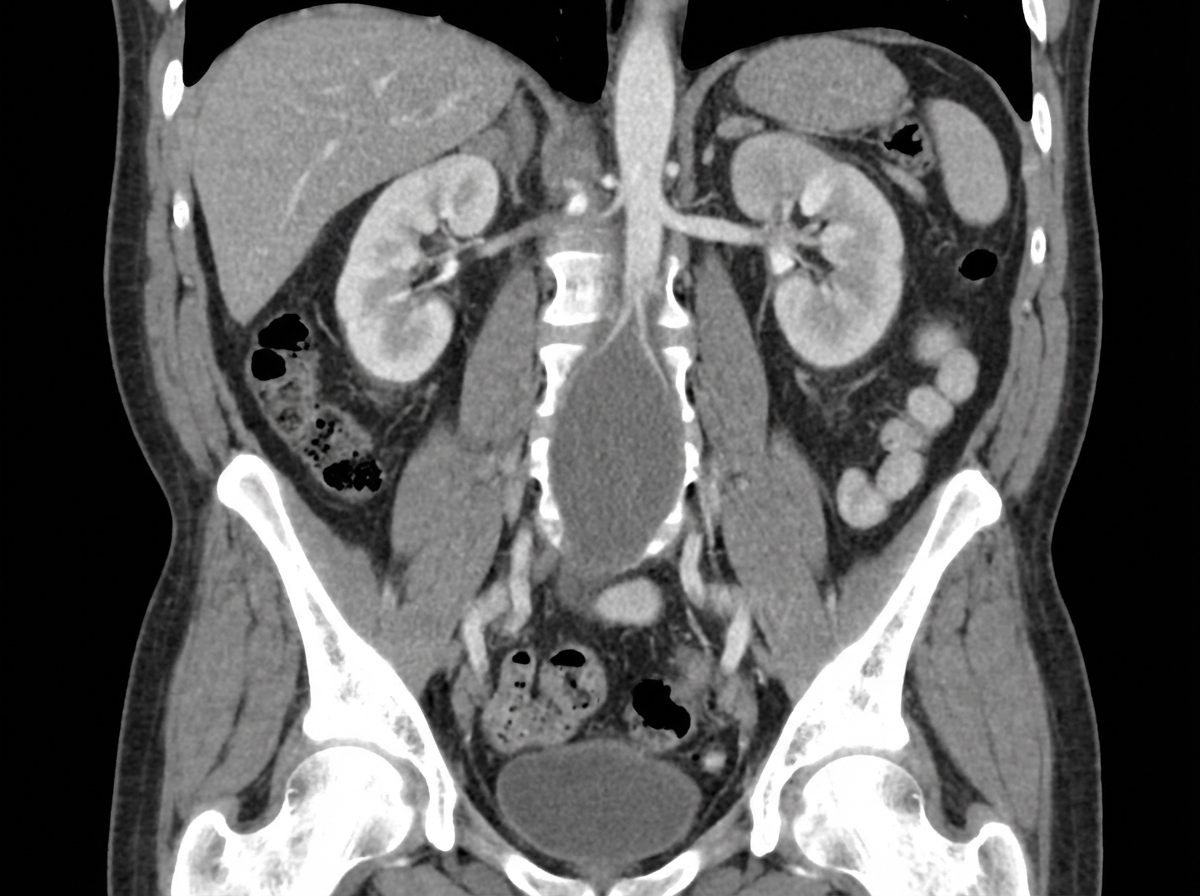

A 70-year-old man presents with right flank pain that radiates to his groin. He has a long history of heavy smoking and alcohol use and reports passing a kidney stone approximately 20 years prior to this event. His past medical history is also remarkable for diabetes mellitus, high cholesterol, and obesity. A computed tomography scan reveals a right 7-mm ureteral stone. In addition, coronal imaging was obtained. Which of the following is the greatest risk factor for the development of additional findings on the imaging study?

Explanation: ***History of smoking*** - **Smoking** is the strongest modifiable risk factor for **abdominal aortic aneurysm (AAA)**, which is the likely incidental finding on coronal CT imaging in this elderly male patient. - **Tobacco use** causes **endothelial dysfunction**, **atherosclerosis**, and **elastin degradation** in the aortic wall, leading to aneurysmal dilatation with a 5-10 fold increased risk compared to non-smokers. *Age* - While **advanced age** (>65 years) is a significant risk factor for AAA, it is less predictive than smoking history in determining aneurysm development. - Age alone without other risk factors has a much lower relative risk compared to the **synergistic effect** of age plus smoking. *History of urolithiasis* - **Kidney stones** are unrelated to the development of **abdominal aortic aneurysms** and do not increase AAA risk. - Prior **urolithiasis** may indicate metabolic abnormalities but has no direct association with **aortic wall pathology**. *Metabolic syndrome* - While **diabetes**, **obesity**, and **hyperlipidemia** contribute to **cardiovascular disease**, they are weaker risk factors for AAA compared to smoking. - **Metabolic syndrome** primarily increases risk through **atherosclerotic mechanisms** but lacks the direct **elastolytic effects** on the aortic wall that smoking provides.